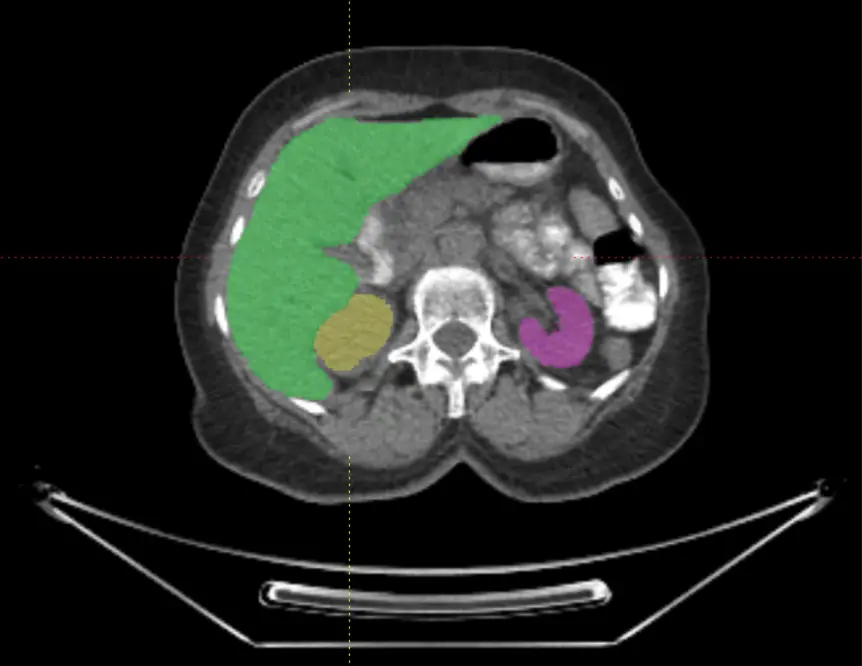

Powered by Voiant Hub 2.0, our platform captures early biological signals and enables advanced, volumetric tumor characterization—unlocking a growing portfolio of imaging biomarkers that refine trial eligibility, accelerate exploratory endpoints, and drive targeted, image-informed strategies:

Radiomics

- Volume

- Shape and Contour Features

- Intensity Features

- Texture Features

- Lesion Heterogeneity

- Rate of Lesion Size Change